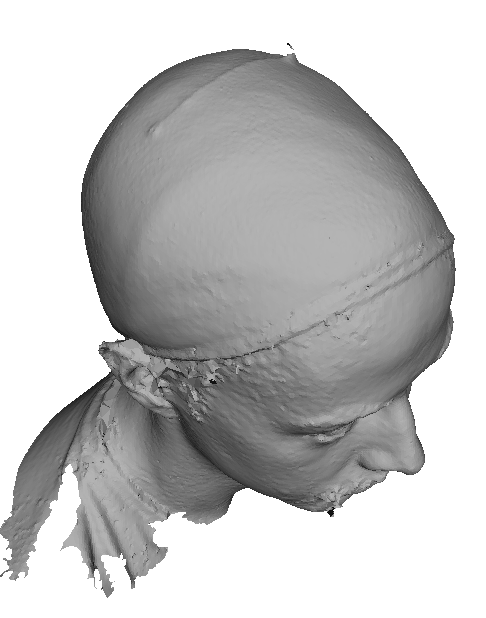

Toolsets to define normal appearance and therefore both assist with planning of surgery and define optimal outcomes from a range of surgical interventions are currently either crude or lacking. Therefore, the unit collected a large, high quality 3D image dataset of 1523 human heads. An example is given in Fig. 1 showing the 3D channel only on the left, and the 3D data with texture pasted on on the right. The data was collected over well-conserved demographics, and an age range of 1 to 89 years, see Fig. 2. The dataset was collected with the aim of developing a normal equivalent of the human cranium and face in order develop the tools to enhance patient experience following surgery. We plan to make the dataset publicly available in the near future.

5.1 Input mesh resolution and mesh reduction

A sample of 100 adult male head scans (without beards) was selected and the number of vertices checked to three significant figures. All scans were between 106 thousand and 180 thousand vertices, with the mean at 143 thousand and the median at 142 thousand vertices. A single scan was selected with close to the mean number of vertices and the vertex-vertex separation checked over the full mesh. The mean and median vertex separation was 1.19mm.

We use the MATLAB reducepatch function to reduce the vertex and face count to around 20% of the original full resolution mesh. The scans now ranged between 20.6k and 37.5k vertices, with the mean at 29.0k vertices and the median at 28.9k vertices. On a sampled scan, the mean vertex separation was 2.86mm and the median 2.72mm. Since the number of vertices reduces by a factor of 5, the mean separation between vertices increases by . This lower resolution allows our landmarking processes to run in a reasonable time in a MATLAB implementation.